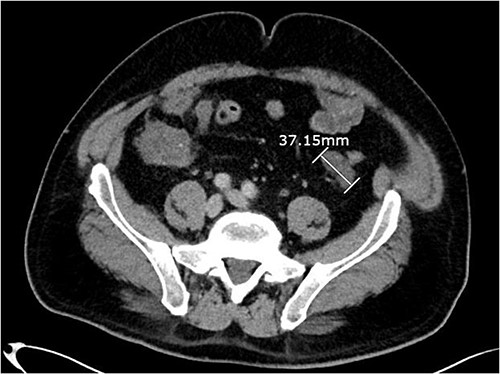

About 1 year later, the patient re-presented for anaemia and underwent a further CT scan. In the right iliac fossa, a 51.96 mm mass was noted such that the appendix could not be visualized separately, with a focus of calcification (Fig. 1). There was infiltration into the adjacent fat and abnormal soft tissue thickening of the peritoneal reflection along the right paracolic gutter. Multiple new peritoneal nodules in the upper abdomen were also identified (Fig. 2). The appearances were in keeping with disseminated malignancy. Following histological analysis, diagnoses of LAMN and PMP was made. The patient was initiated on mitomycin and capecitabine chemotherapy, which modestly reduced the size of the right iliac fossa mass from 51.96 mm to 44.23 mm (Fig. 3).

Axial CT abdomen with contrast demonstrating an appendiceal mass of maximum diameter 51.96 mm.